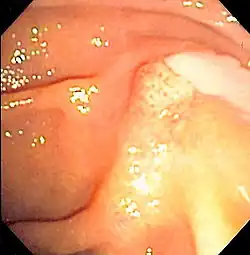

![]() | |

| Duodenoscopy image of pus extruding from the ampulla of Vater, indicative of cholangitis | |

The gold standard test for biliary obstruction is still endoscopic retrograde cholangiopancreatography (ERCP). This involves the use of endoscopy (passing a tube through the mouth into the esophagus, stomach and thence to the duodenum) to pass a small cannula into the bile duct. At that point, radiocontrast is injected to opacify the duct, and X-rays are taken to get a visual impression of the biliary system. On the endoscopic image of the ampulla, one can sometimes see a protuberant ampulla from an impacted gallstone in the common bile duct or the frank extrusion of pus from the common bile duct orifice. On the X-ray images (known as cholangiograms), gallstones are visible as non-opacified areas in the contour of the duct. For diagnostic purposes, ERCP has now generally been replaced by MRCP. ERCP is only used first-line in critically ill patients in whom delay for diagnostic tests is not acceptable; however, if the index of suspicion for cholangitis is high, an ERCP is typically done to achieve drainage of the obstructed common bile duct.[1]